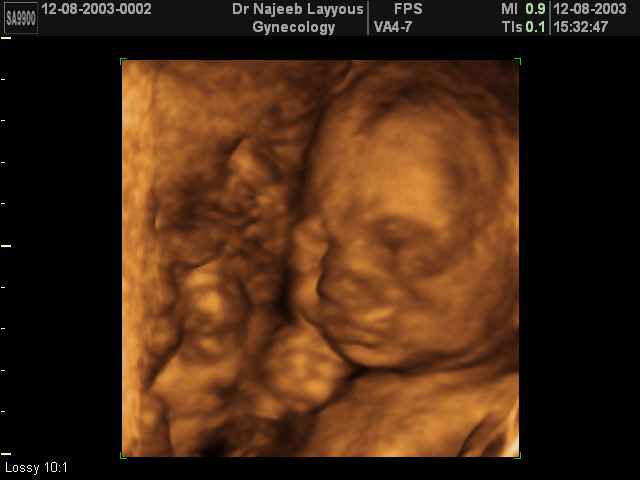

- تصرفات الجنين داخل الرحم

- صور لوجه الجنين في داخل الرحم

- صور لتصرفات الجنين داخل الرحم

صور لتصرفات الجنين داخل الرحم بجهاز الالتراساوند ثلاثي الأبعاد | الدكتور نجيب ليوس